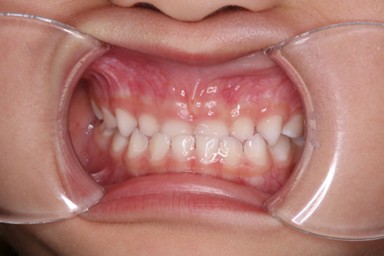

| 主訴 | 受け口を治したい。 |

| 治療内容 | ・使用装置:- マイオブレース(J1, J2) ・ワイヤー矯正および拡大装置等:未使用 ・抜歯:なし |

| 治療費 | 110,000円(税込み) |

| 治療期間 | 2017年9月~2018年8月(現在も定期的に保険にて観察中) |

| 治療回数 | 10回 |

| 想定されたリスク | マイオブレースの装着状況によっては結果が得られず、その他の矯正器具を使用する可能性がありました。 |

乳歯の反対咬合は様子を見ましょうと言われることが多いですが、上顎の前方発育を阻害する大きな要因となりますので、早期の介入をおすすめしています。反対咬合は1年で改善し、現在は定期健診で様子を見ています。装置を付けることなく、良好に生え変わりが進んでいます。